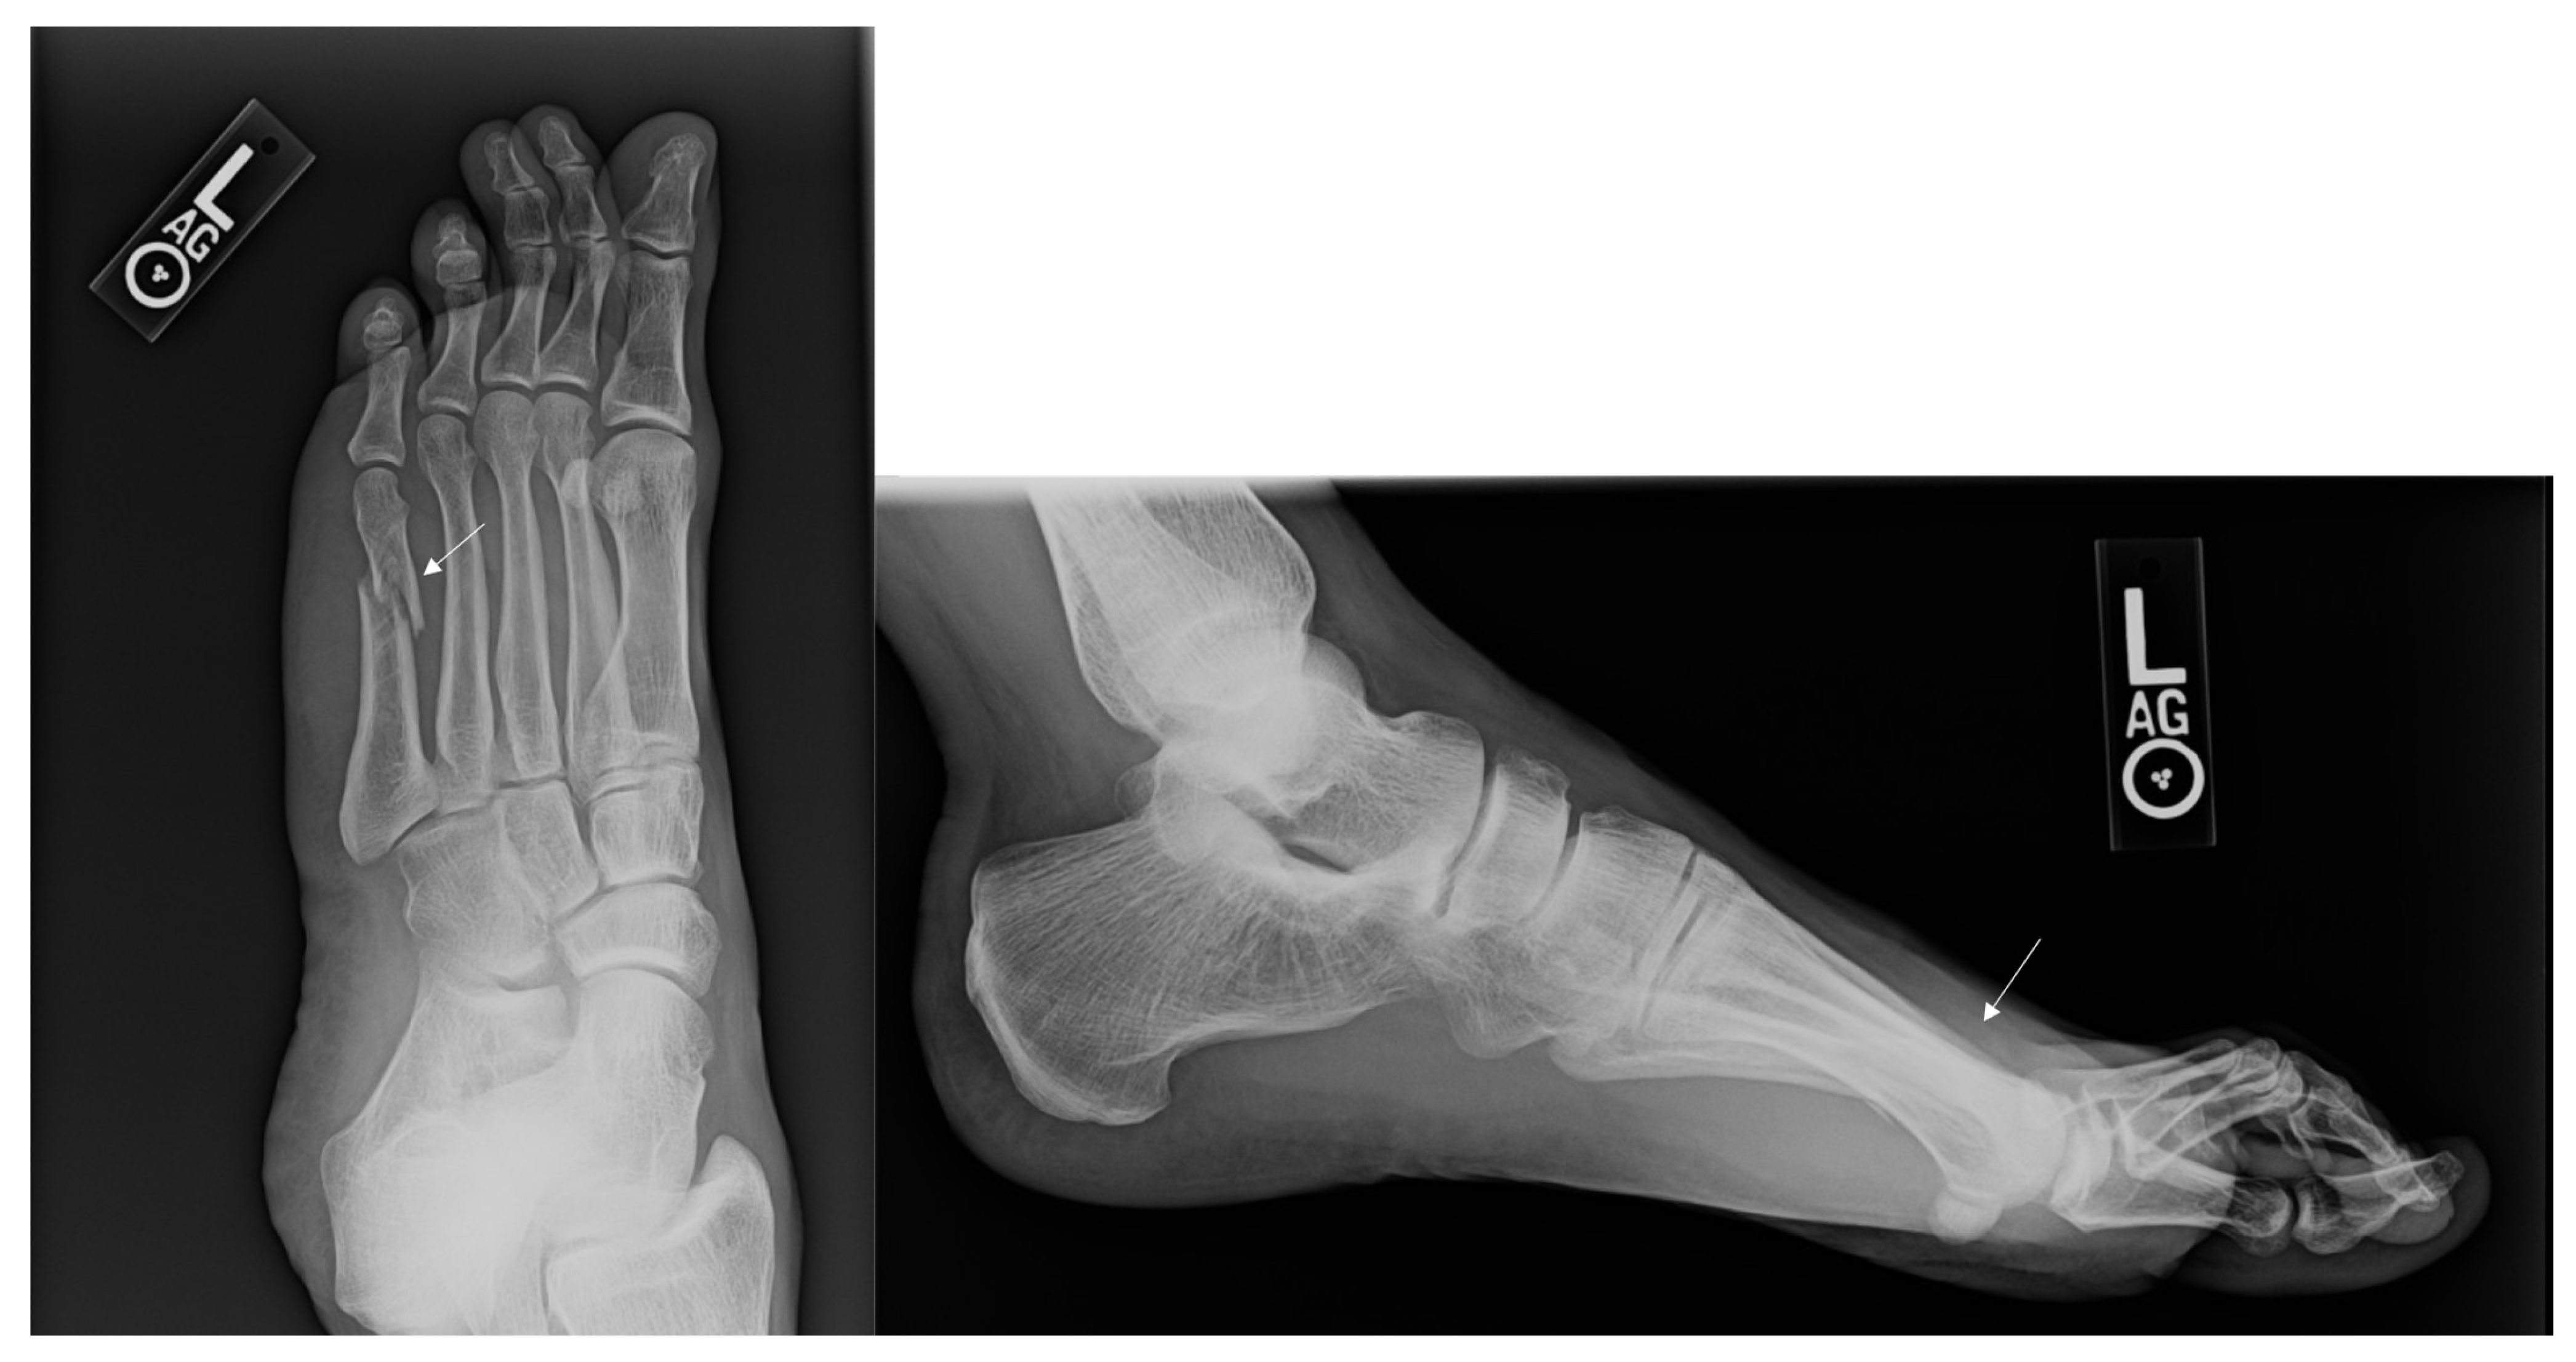

Figure 1.

Injury Films for Displaced Metatarsal Fractures from a Gunshot. Displayed above are the injury radiographs for second and third metatarsal fractures following a gunshot injury. The arrows above identify the metatarsal fractures.

Figure 2.

Post-operative Images for Displaced Non-union. Displayed above are the radiographs for second and third metatarsal fractures following a gunshot injury that underwent ORIF due to a non-union.